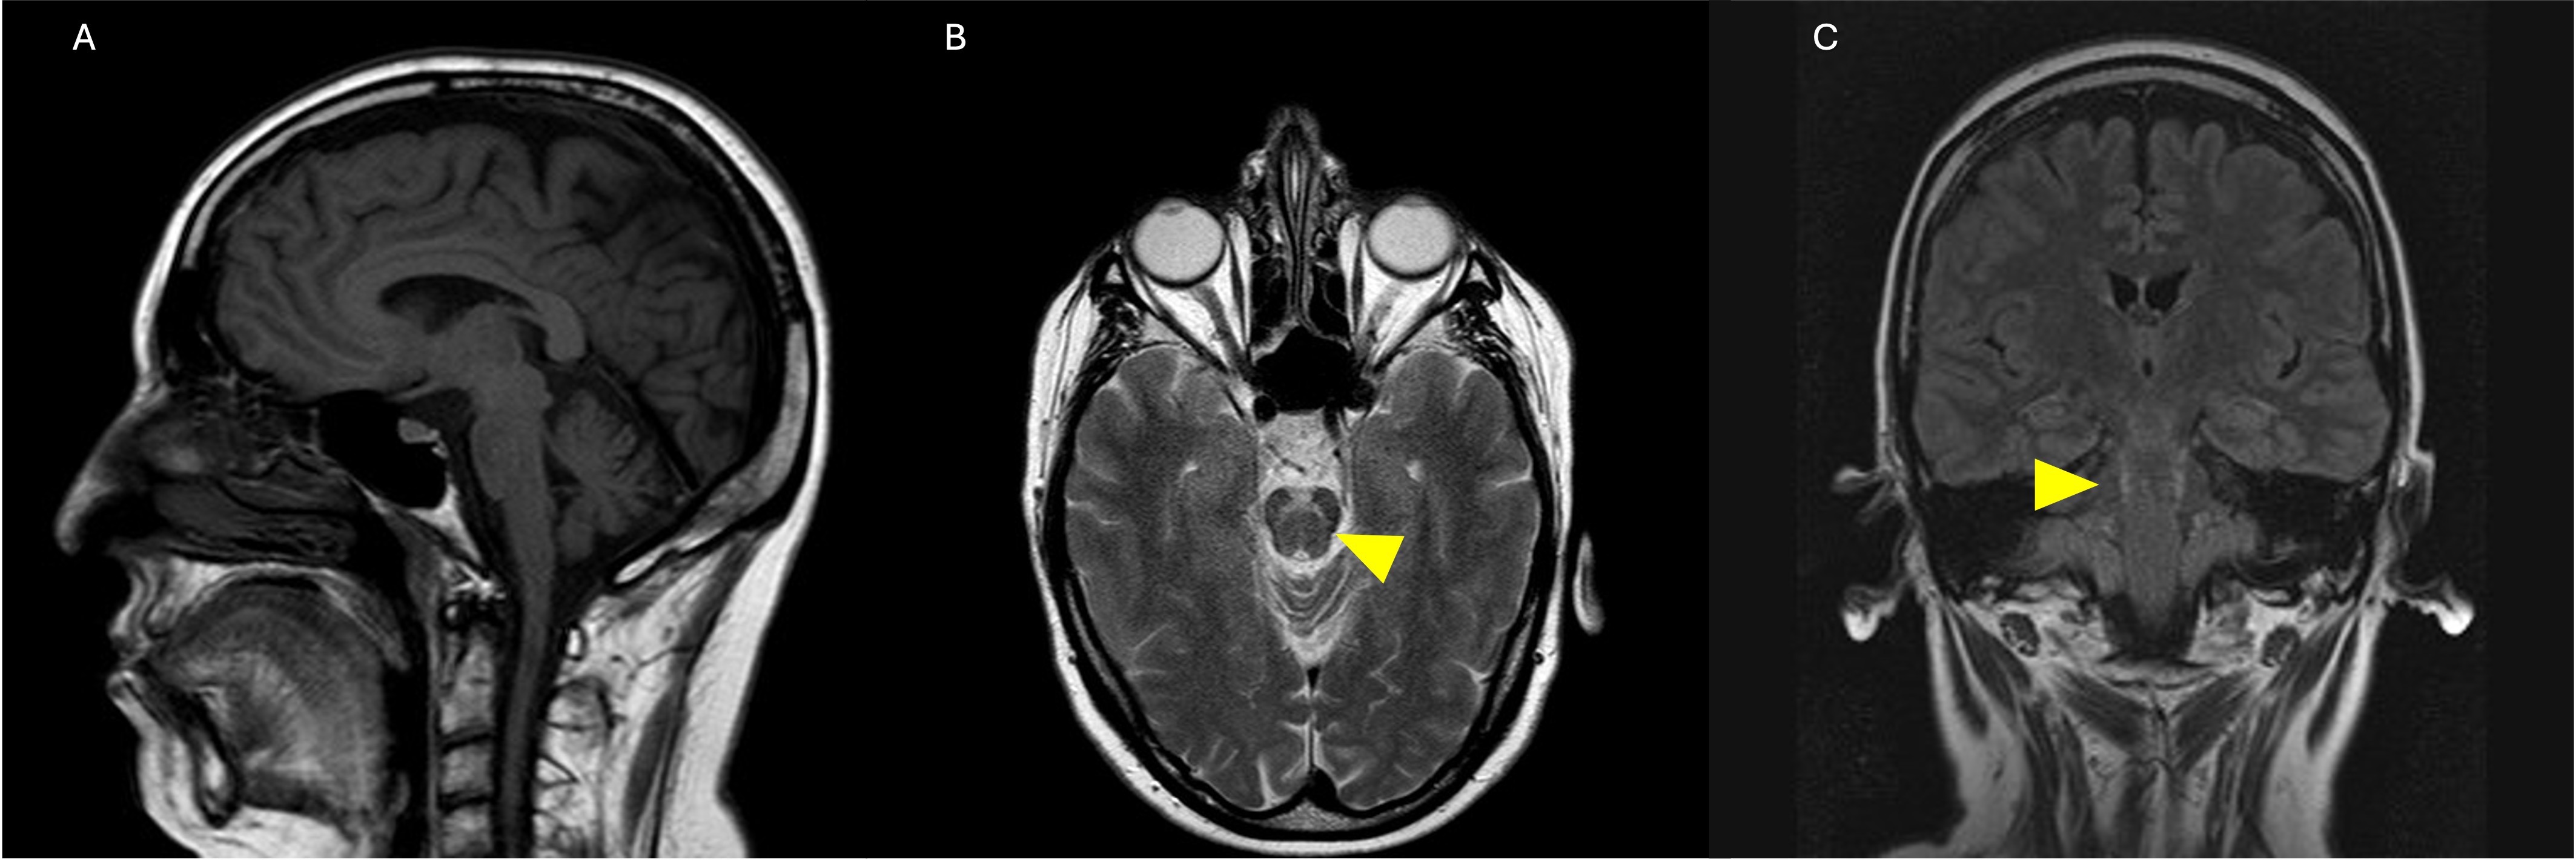

Results: Pedigree of the family is shown in [figure1]. The sister (III:4) had tonic-clonic seizures from 20, with myoclonic tremor, gait difficulties, and cognitive decline by 52. Despite medication, her seizures were only partially controlled. She passed away at 62.MRI showed T2 hyperintensity in the pyramidal tract and mild cerebellar atrophy.The proband (III:3) had seizures from 20 and developed generalized myoclonic tremor and cognitive decline by 64, requiring a wheelchair by 50.The nephew (IV:7) and the daughter (IV:6) had controlled seizures with mild EEG abnormalities. Genetic testing in III:3, IV:7 and IV:6 showed a TTTTA/TTTCA repeat expansion in MARCH6.

Cerebellar atrophy and T2-hyperintensity in pons